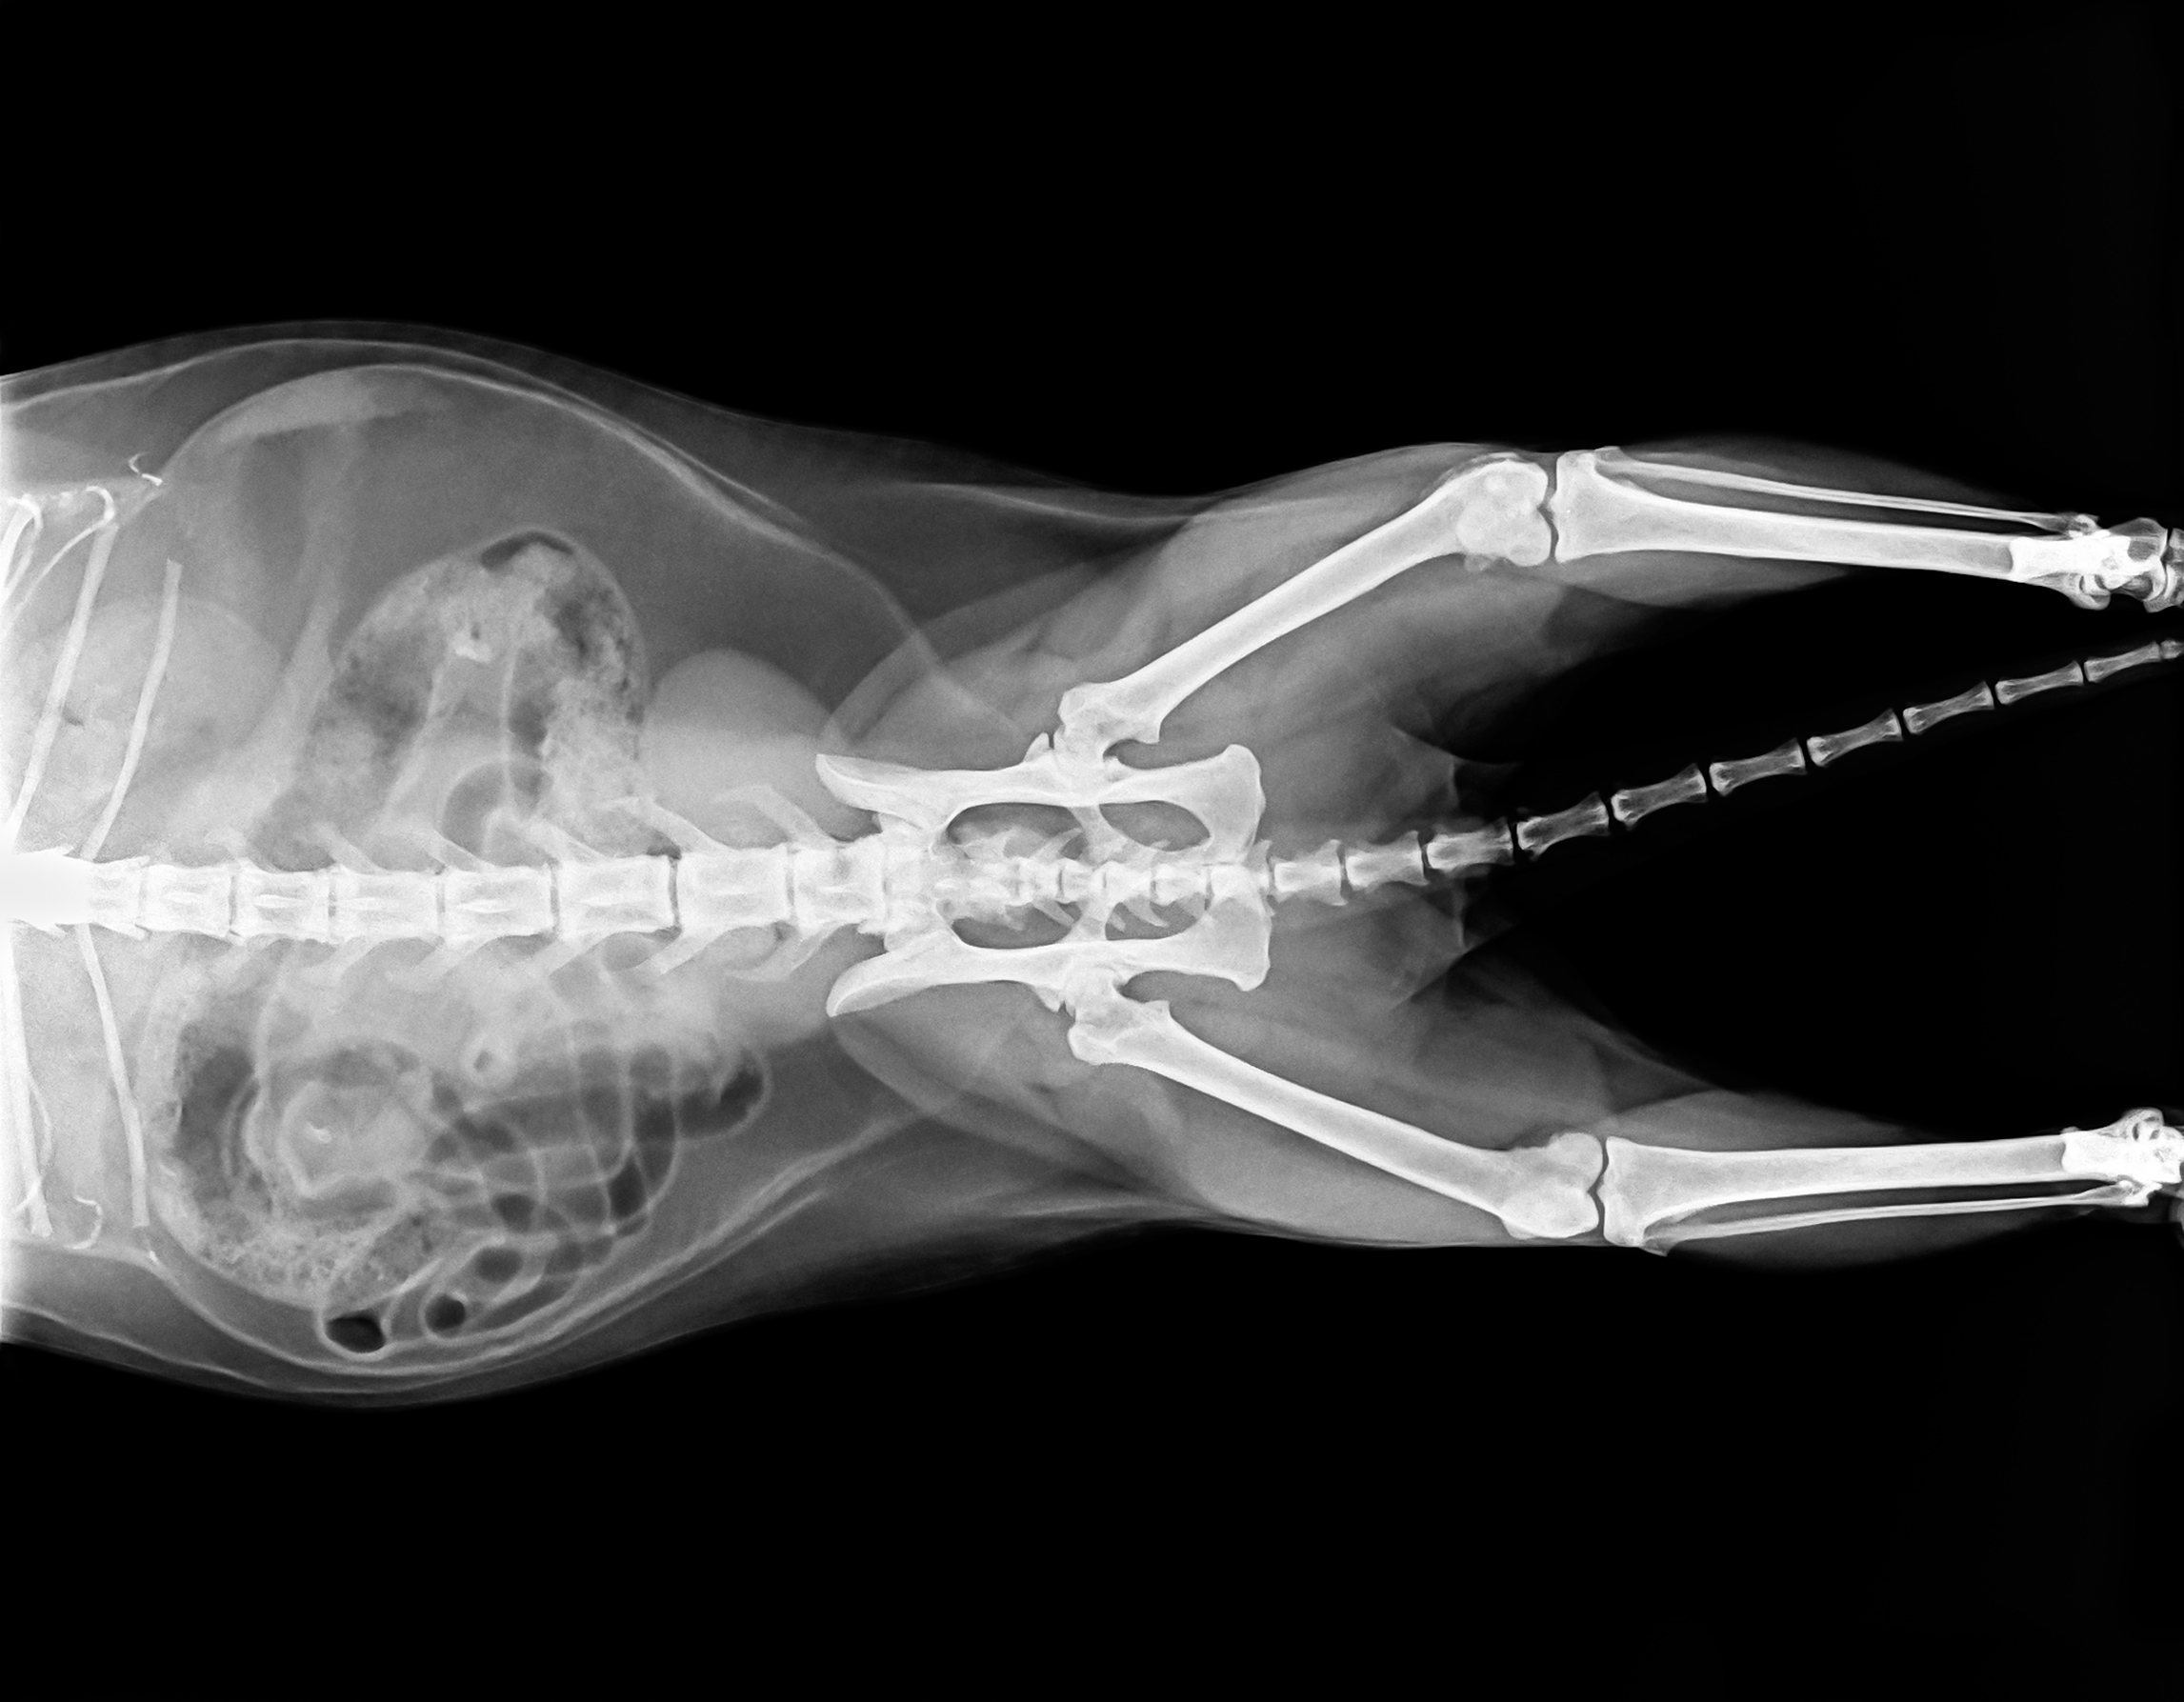

Рентгеновские снимки анатомии собак: строение и здоровье